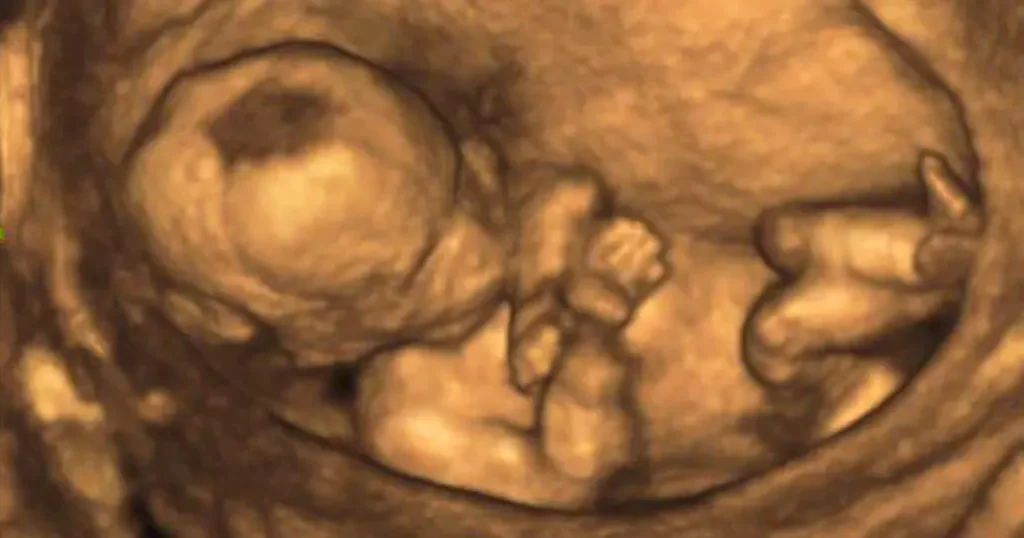

Was ist ein großer Ultraschall?

Ein großer Ultraschall, auch als fetale Ultraschalluntersuchung bezeichnet, ist eine bildgebende Untersuchung, die mithilfe von Schallwellen ein detailliertes Bild deines Babys im Mutterleib erzeugt. Der Ultraschall ist ein sicheres und schmerzloses Verfahren, das keine schädlichen Strahlen verwendet. Er spielt eine wichtige Rolle in der Schwangerschaftsvorsorge und ermöglicht es den Ärzten, die Entwicklung deines Babys genau zu beobachten und eventuelle Auffälligkeiten frühzeitig zu erkennen.

Was passiert beim großen Ultraschall?

Der große Ultraschall wird in der Regel von deinem Frauenarzt durchgeführt. Bei der ersten Untersuchung wird der Ultraschall noch vaginal durchgeführt, bei den späteren Untersuchungen wird ein Gel auf deinen Bauch aufgetragen, um die Schallwellen besser durch die Haut leiten zu können.

- Die Untersuchung: Der Frauenarzt wird den Ultraschallkopf auf deinen Bauch oder in die Scheide legen. Während der Untersuchung wird er verschiedene Bilder deines Babys aufnehmen und diese auf dem Bildschirm des Ultraschallgeräts betrachten.